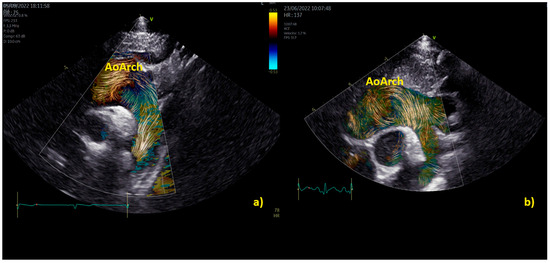

A study [8] of BST in 14 children with bicuspid aortic valve (BAV) < 10 years of age and 24 age-matched controls revealed how children with bicuspid aortic valve exhibit altered flow dynamics in the aortic root and left ventricle in the absence of significant aortic root dilation (and with mild or no regurgitation and/or stenosis). Children with BAV [8] had on average higher aortic root vorticity (e.g., mean 25.9 Hz, range 23.4–29.2 Hz vs. mean 17.8 Hz, range 9.0–26.2 Hz, p < 0.05), vector complexity (e.g., 0.17, 0.14–0.31 vs. 0.05, 0.02–0.13, p < 0.01), and rate of energy loss (e.g., mean 7.9 mW/m, range 4.9–12.1 mW/m vs. mean 2.7 mW/m, range 1.2–7.4 mW/m, p = 0.01). In children with bicuspid aortic valve, there was higher left ventricular average diastolic vorticity (e.g., 20.9 ± 5.8 Hz vs. 11.4 ± 5.2 Hz, p < 0.01), kinetic energy (e.g., 0.11 ± 0.05 J/m vs. 0.04 ± 0.02 J/m, p < 0.01), vector complexity (e.g., 0.38 ± 0.1 vs. 0.23 ± 0.1, p < 0.01), and rate of energy loss (e.g., 11.1 ± 4.8 mW/m vs. 2.7 ± 1.9 mW/m, p < 0.01) [8] Table 4.

Practical examples of differences among physiological and pathological aortic vortices are provided in Figure 5. In Figure 5a, a physiological vortex is shown, while in Figure 5b, an example of a big vortex in the dilated ascending aorta of a child with a bicuspid aortic valve with moderate stenosis has been provided. The propagation of the vortex in the aortic arch in physiological condition and in a child with bicuspid aortic valve with moderate stenosis is shown in Figure 6. In the example, it appears clear that the vortex of the healthy patient (Figure 6a) occupies a smaller area than the pathological vortex and is localized on the ventral surface of the aortic arch, below the first two epi-aortic branches. On the contrary, the vortex of the child with bicuspid aortic valve valvular stenosis (Figure 6b) is located proximal to the epi-aortic branches and occupies the great part of a dilated transverse arch.

Figure 5. Vortex in the aorta of a healthy child (a) and in a patient with a bicuspid aortic valve causing moderate stenosis (b) The vortex develops at the end of diastole in both patients, but while in the healthy subject (a), physiologically we have a vortex inside the aortic root (AoRoot), in the child with bicuspid aortic valve (b), due to the stenosis, the vortex develops more distally, above the sinus-tubular junction, and it is bigger than its healthy counterpart. AoRoot = aortic root, LA = left atrium; LV = left ventricle; MV = mitral valve; RA = right atrium; RV = right ventricle.